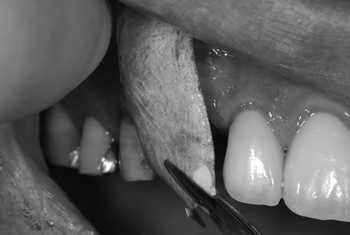

歯ぎしりの強い方で、歯が割れたということで来院されました。強い歯ぎしりは歯をすり減らしたり歯冠や歯根を破壊するだけでなく、時には歯を支える歯槽骨という骨にも歪を生じさせることがあります。割れた歯をの残根を除去し、骨造成を行った上でインプラント治療を行いました。

メンブレンという特殊な膜で骨を作る処置(骨造成)を行う骨造成です。

Process